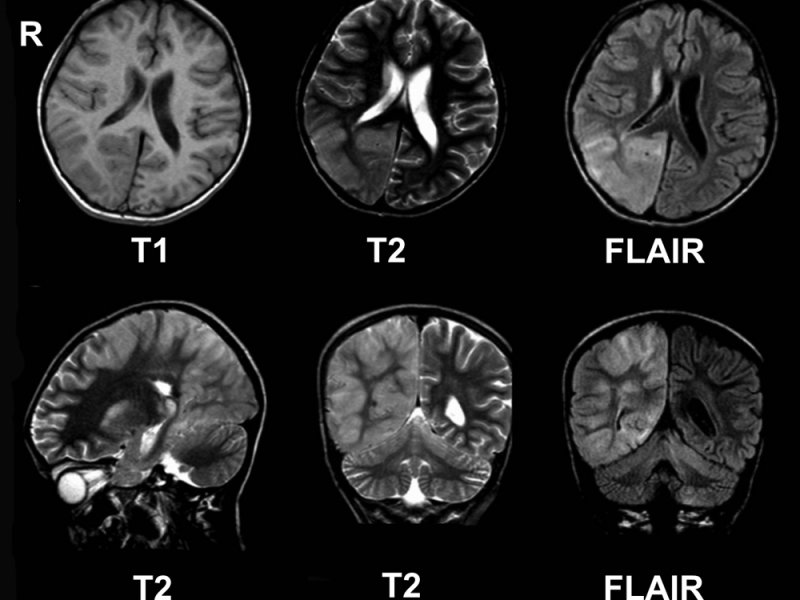

Исследователи из Калифорнийского университета в Дэвисе предложили усовершенствование для магнитно-резонансной томографии (МРТ), которое позволит обнаруживать даже очень маленькие опухоли. Работа была опубликована в журнале Nature Nanotechnology.

Исследование основано на магнитно-резонансной настройке, которая происходит между двумя магнитными элементами нано размера. Один действует для усиления сигнала, а другой гасит его. Предыдущие исследования показали, что гашение зависит от расстояния между магнитами. Это открывает новые возможности для неинвазивного и чувствительного исследования множества биологических процессов с помощью МРТ.

Команда создала химический зонд, который генерирует два магнитно-резонансных сигнала, подавляющих друг друга до достижения цели. При подходе к ней оба увеличивают контраст между опухолью и окружающей тканью. Ученые назвали технологию двусторонней магнитно-резонансной настройкой (TMRET).

В сочетании со специально разработанным программным обеспечением для анализа изображений, двойной сигнал позволил исследователям быстрее выявить небольшие опухоли головного мозга у мышей.